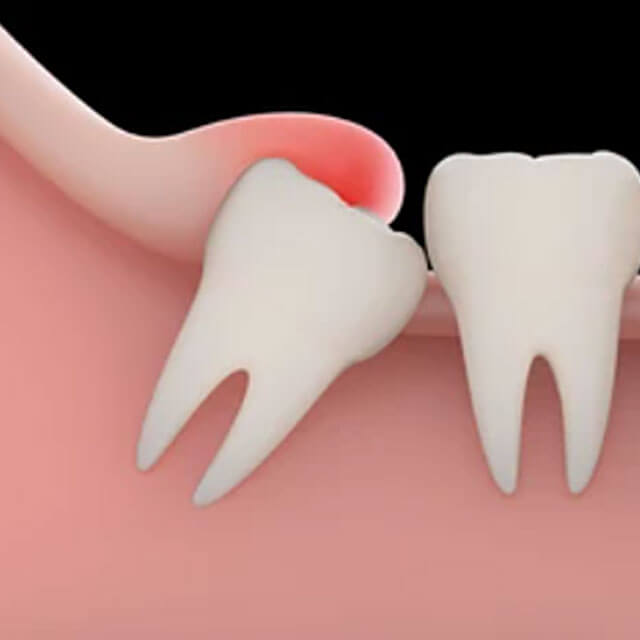

しかし、私たち現代人は古代人と比べ顎が小さくなっており、親知らずが適切に生えるスペースが足りないことが多く、その結果、親知らずが斜めに生えてきたり、埋まったままの生えない状態になっていることがあります。

歯磨きによる清掃が困難であるため、プラークを落としきれず、親知らずそのものや隣接する歯にむし歯や歯周病が生じる。

親知らずが本来とは異なった方向に生えることで、周囲の組織を傷つけて炎症を招く。

2,痛みがなくても親知らずが斜めに生えている方

歯ブラシでの汚れの清掃が難しいため、隣の歯のむし歯や歯周病を引き起こすリスクが高いです。